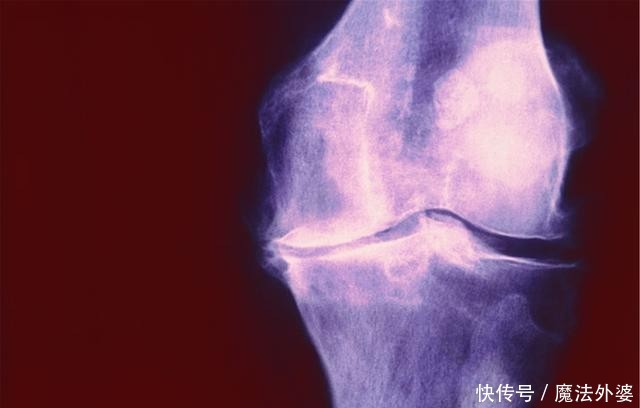

1、骨头痛骨质疏松会直接导致骨质量下降,因此引发骨骼方面的疼痛是最明显的,在生活中老年人可以感觉到在活动过程中会有明显的痛感,这种痛感会逐渐加强,并且影响到老年人的活动功能。这通常就是骨质疏松导致的骨痛症状,而且有的严重的患者在不活动的时候也会有明显的骨痛。2、口腔部位疼痛骨质疏松还会导致老年人口腔部位的疼痛,因为骨质疏松会导致牙齿松动和脱落,有的时候就会影响到周围组织健康,在进食的时候会加强对口腔的刺激。因此,在患上骨质疏松的时候,老年患者通常就会有牙齿疼痛的症状,除此之外口腔也更容易受到外界因素的影响引发疼痛。3、关节疼痛关节疼痛是骨质疏松的早期症状,因为在早期的时候骨质量明显下降,关节能够承担的压力也就下降了,在进行活动的时候,患者会有明显的关节酸痛问题。不仅如此,老年人本身关节就容易磨损,所以在活动的时候,关节的烧灼痛感或者刺痛感会更明显。如果是患有关节炎的老年人,疼痛症状会变得比较剧烈。